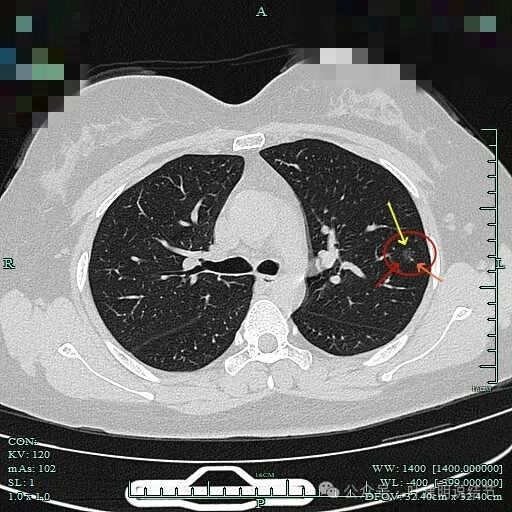

血管贴边走行,并形成血管弯征。灶内密度略不均。

血管改变走行,边缘毛刺。

边缘区域病灶有微小血管进入,也有细支气管扩张征。